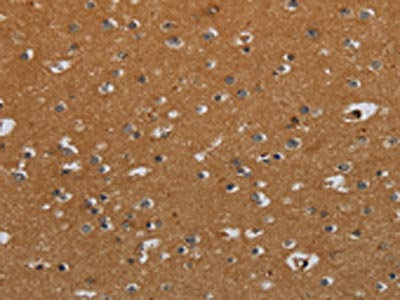

The image on the left is immunohistochemistry of paraffin-embedded Human brain tissue using CSB-PA077659(CSH1 Antibody) at dilution 1/40, on the right is treated with fusion protein. (Original magnification: ×200)